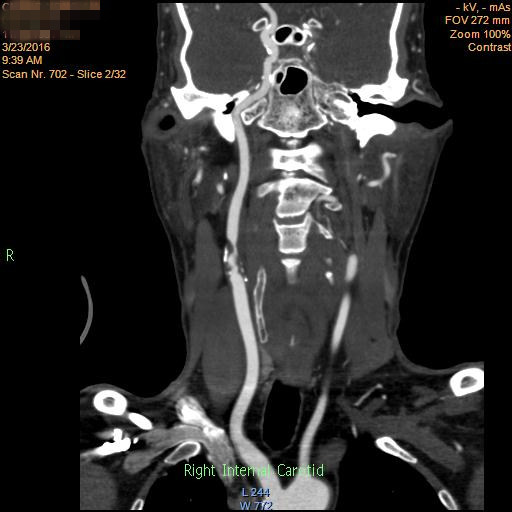

这是一位64岁的老年男性患者,反复头晕4年,症状最重时不能下床行走,严重影响日常生活,在当地医院定期输液治疗,仍无法减轻症状。2周前,症状明显加重,头晕发作频繁,站立即出现头晕加重,终日卧床,非常痛苦,输液治疗不能缓解。在当地医院行头颅SCT提示多发脑梗死,行颈部血管检查提示颅外动脉多发硬化、狭窄性病变。经多方打听,患者来到了郑大五附院血管外科住院治疗,颈部及头颅CTA提示颅外动脉多发硬化性病变,其中右颈动脉重度狭窄,左颈动脉、右椎动脉纤细,近似闭塞,左椎动脉开口处重度狭窄,左侧颅内动脉烟雾病样表现,供应颅脑血供的4支重要血管都不同程度地出了问题,且左侧颅内血管也存在问题,这说明颅脑严重缺血,随时可能发生脑梗死、脑血栓等致命性危害,治疗刻不容缓!但所有的血管又不可能同时处理,那究竟先处理哪一支呢?而哪些动脉是不需要处理的呢?开通颅外血管后对颅内动脉的影响有多大,患者脆弱的大脑能不能承受呢?一系列问题摆在了医生面前。在王兵副院长的带领下,血管外科全体医师进行了激烈的讨论,为患者制定了一个可行的治疗方案,由于左颈内动脉及右椎动脉纤细,开通对患者颅内血供的意义不大,所以可后期处理,右颈动脉和左椎动脉开通的意义较大,结合患者症状优先开通供应前循环的右颈动脉更为妥当,且患者左颅脑动脉烟雾病样表现,所以开通右颈动脉导致脑出血的风险较小,由于多支病变,为了避免阻断导致脑梗死风险,手术方式选为支架置入术理所当然,但右颈动脉的斑块性质不良,存在溃疡斑块可能,一旦溃疡斑块被支架挤碎就会发生右侧大脑半球的栓塞事件发生,所以对腔内的操作技巧要求极高。这就相当于在一个摇摇欲坠的房屋中加支撑柱,搞不好就会因为操作不当造成房屋的彻底坍塌。但王兵副院长带领的团队对此信心满满,这种自信来源于丰富的临床经验、恰当的治疗策略、高超的手术技巧和来自患者的绝对信任。

术前CTA